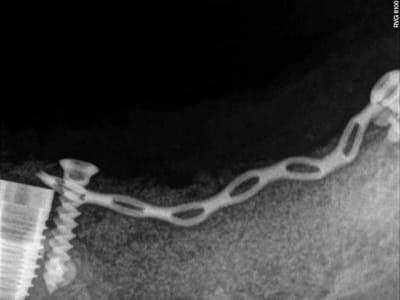

j'en viens maintenant au système FAST de Joseph.

1- les vis et la chaine titane adaptée aux vis.

(pour expliquer: ce système permet de maintenir la chaîne en l'air par sa tête.)

4-5-6-7 sciage de la mesh titane et positionnement in situ d'un bout à l'autre de l'arcade.